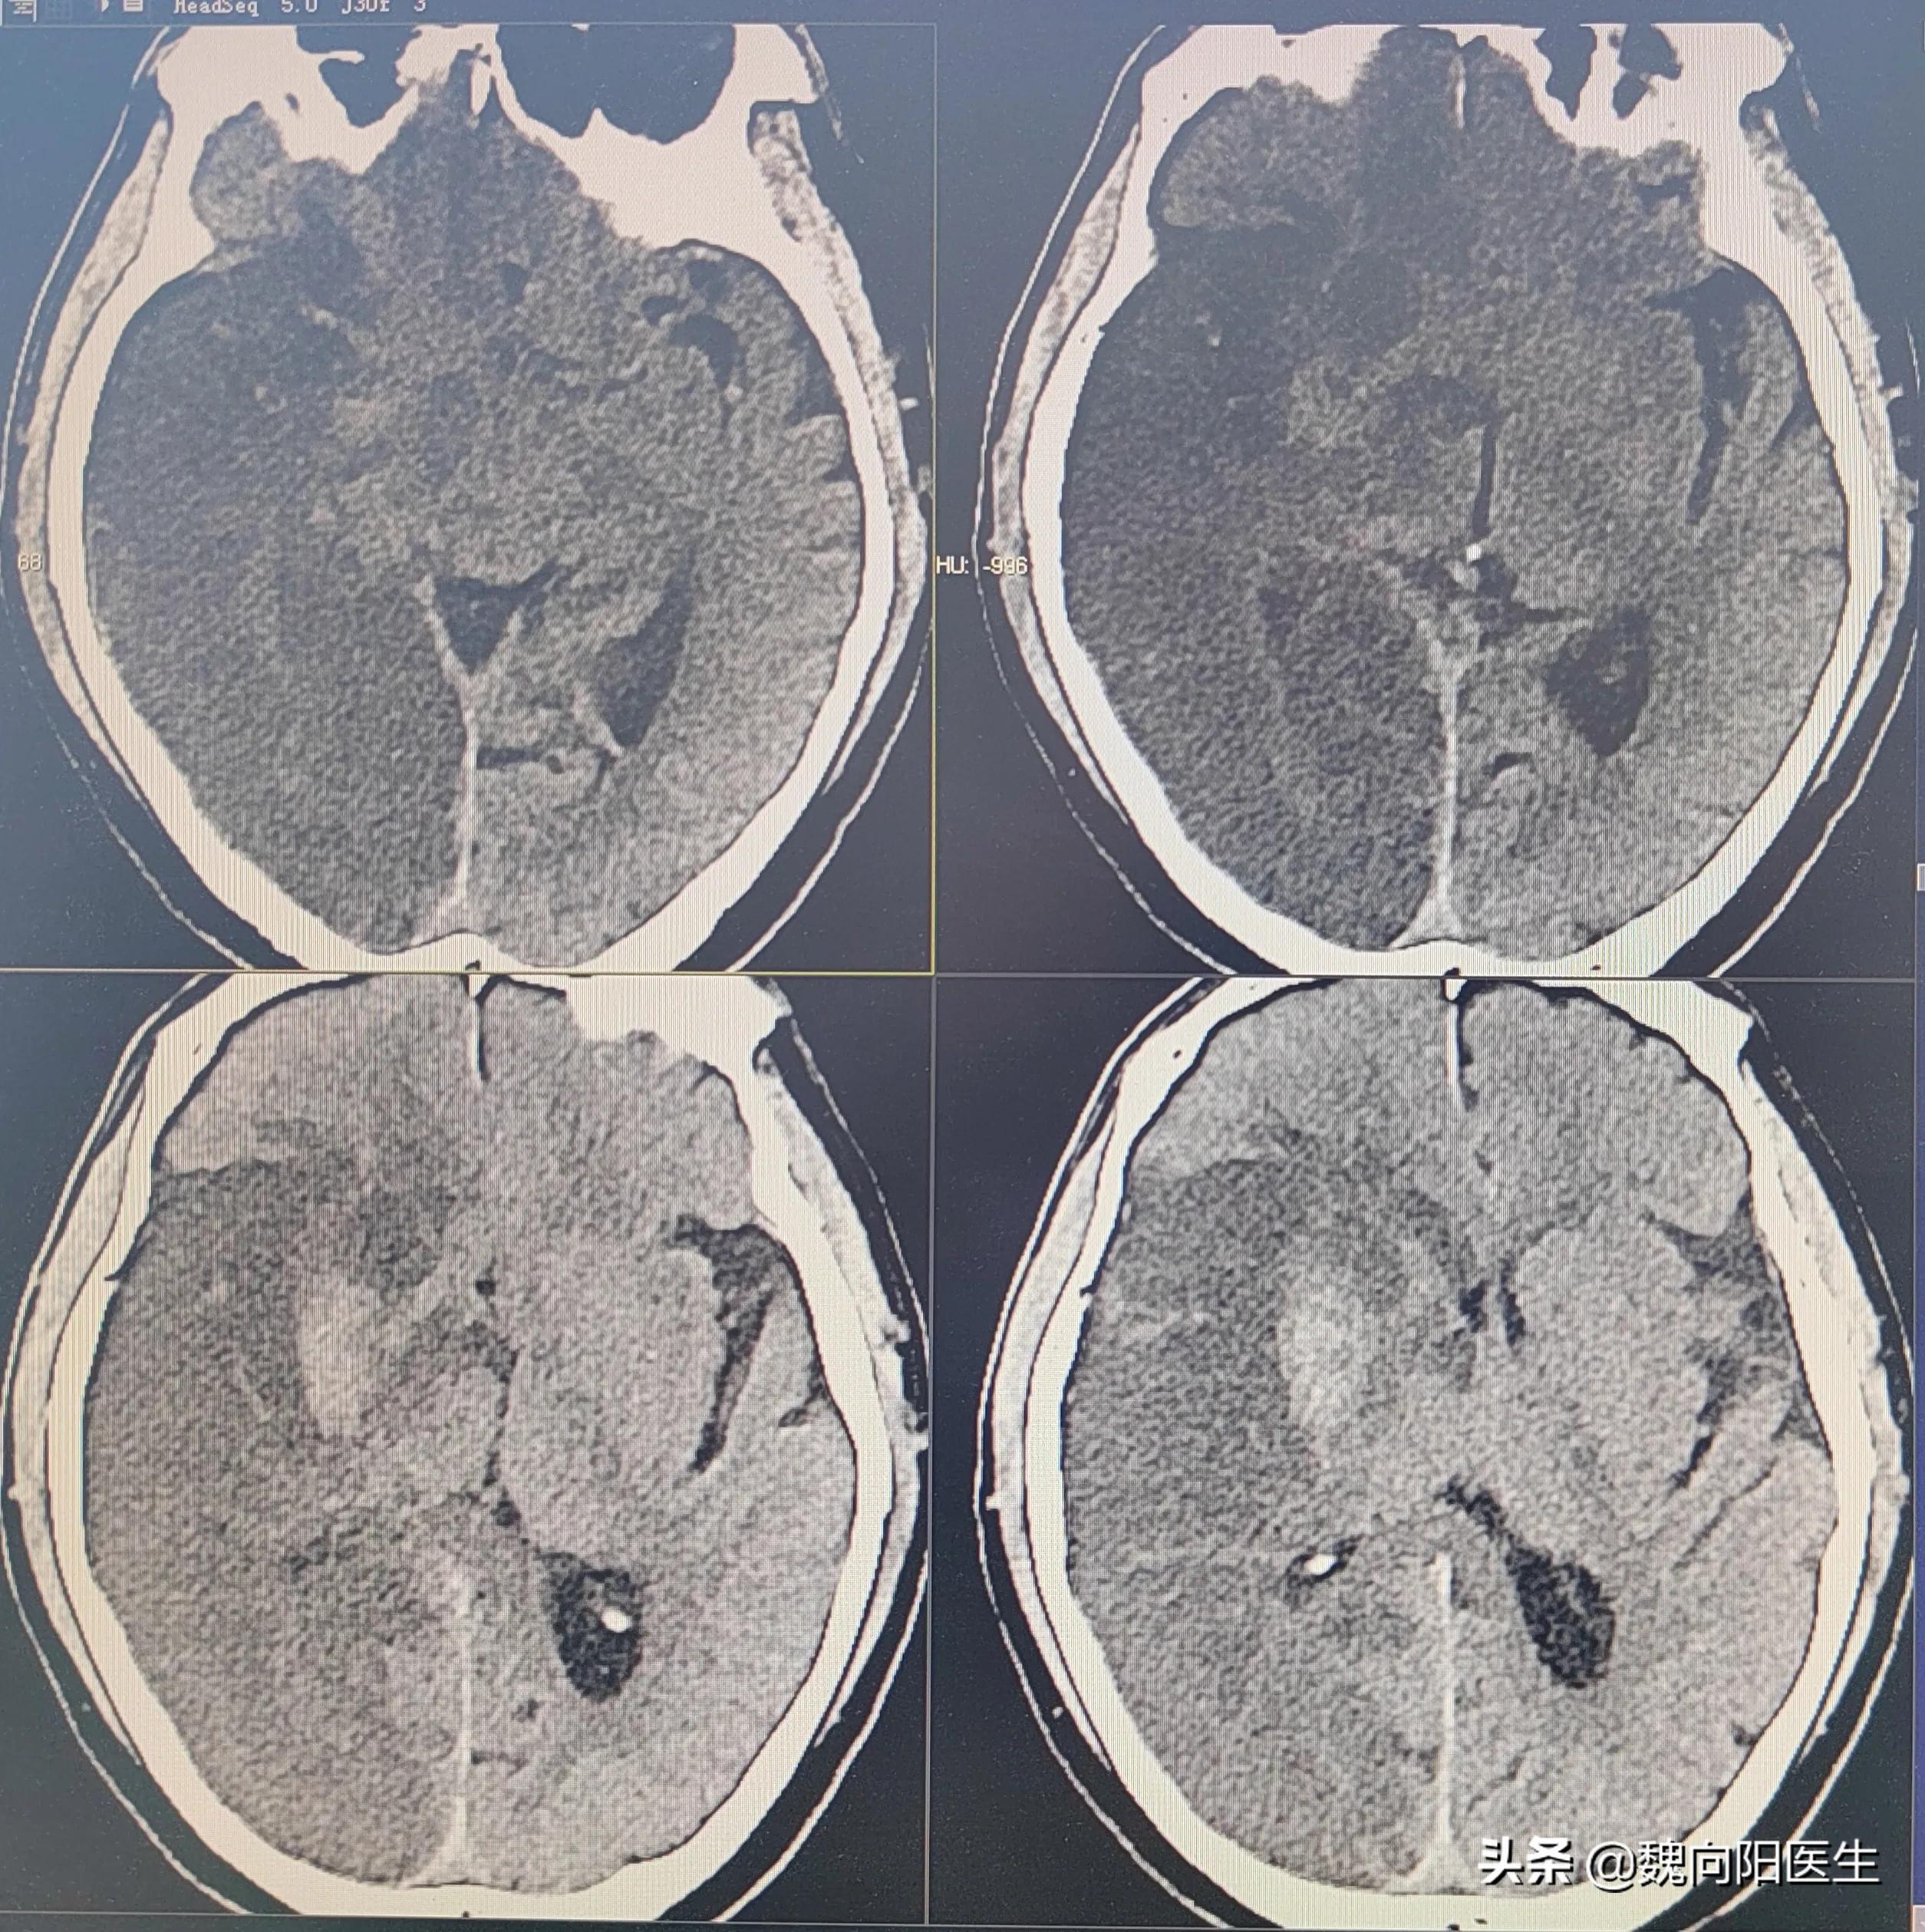

大面积脑梗死

一旦出现大面积脑梗死,随着脑细胞肿胀,颅内压会越来越高,导致继发性损害,恶性循环,会进一步加重其他脑细胞的缺血缺氧,最终危及生命。

针对这种情况,再去取血栓已经没有意义,终极办法,只能开颅去骨瓣减压,尽可能保护尚未坏死细胞,优先保命,至于是否遗留后遗症,先不要管。